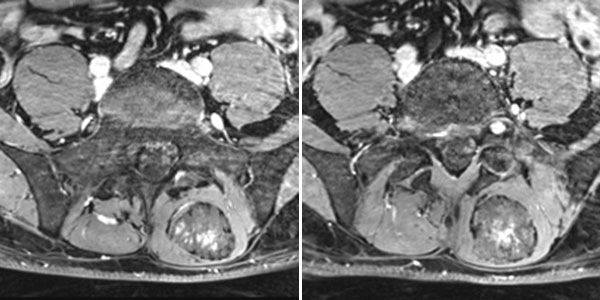

The lesion is very clearly visible in the MRI in coronal plane. In the T2-weighted sequence with fat saturation (left), the lesion is highly hyperintense (white). In the non-enhanced T1-weighted sequence (right), it is virtually isointense to the surrounding back muscle. Note here the fatty tissue visible marginally in the lesion, hyperintense in T1 weighting.

In dynamic contrast-enhanced MR angiography (late phase over 2 min after contrast administration, left coronal and right sagittal), the lesion shows no contrast enhancement or increased vascularization. It is practically invisible.

In the axial, fat-saturated T1-weighted images after contrast medium administration, an initially inhomogeneous accumulation of contrast medium in terms of contrast pooling occurs only slowly and incompletely. This is also relatively typical of a venous malformation.